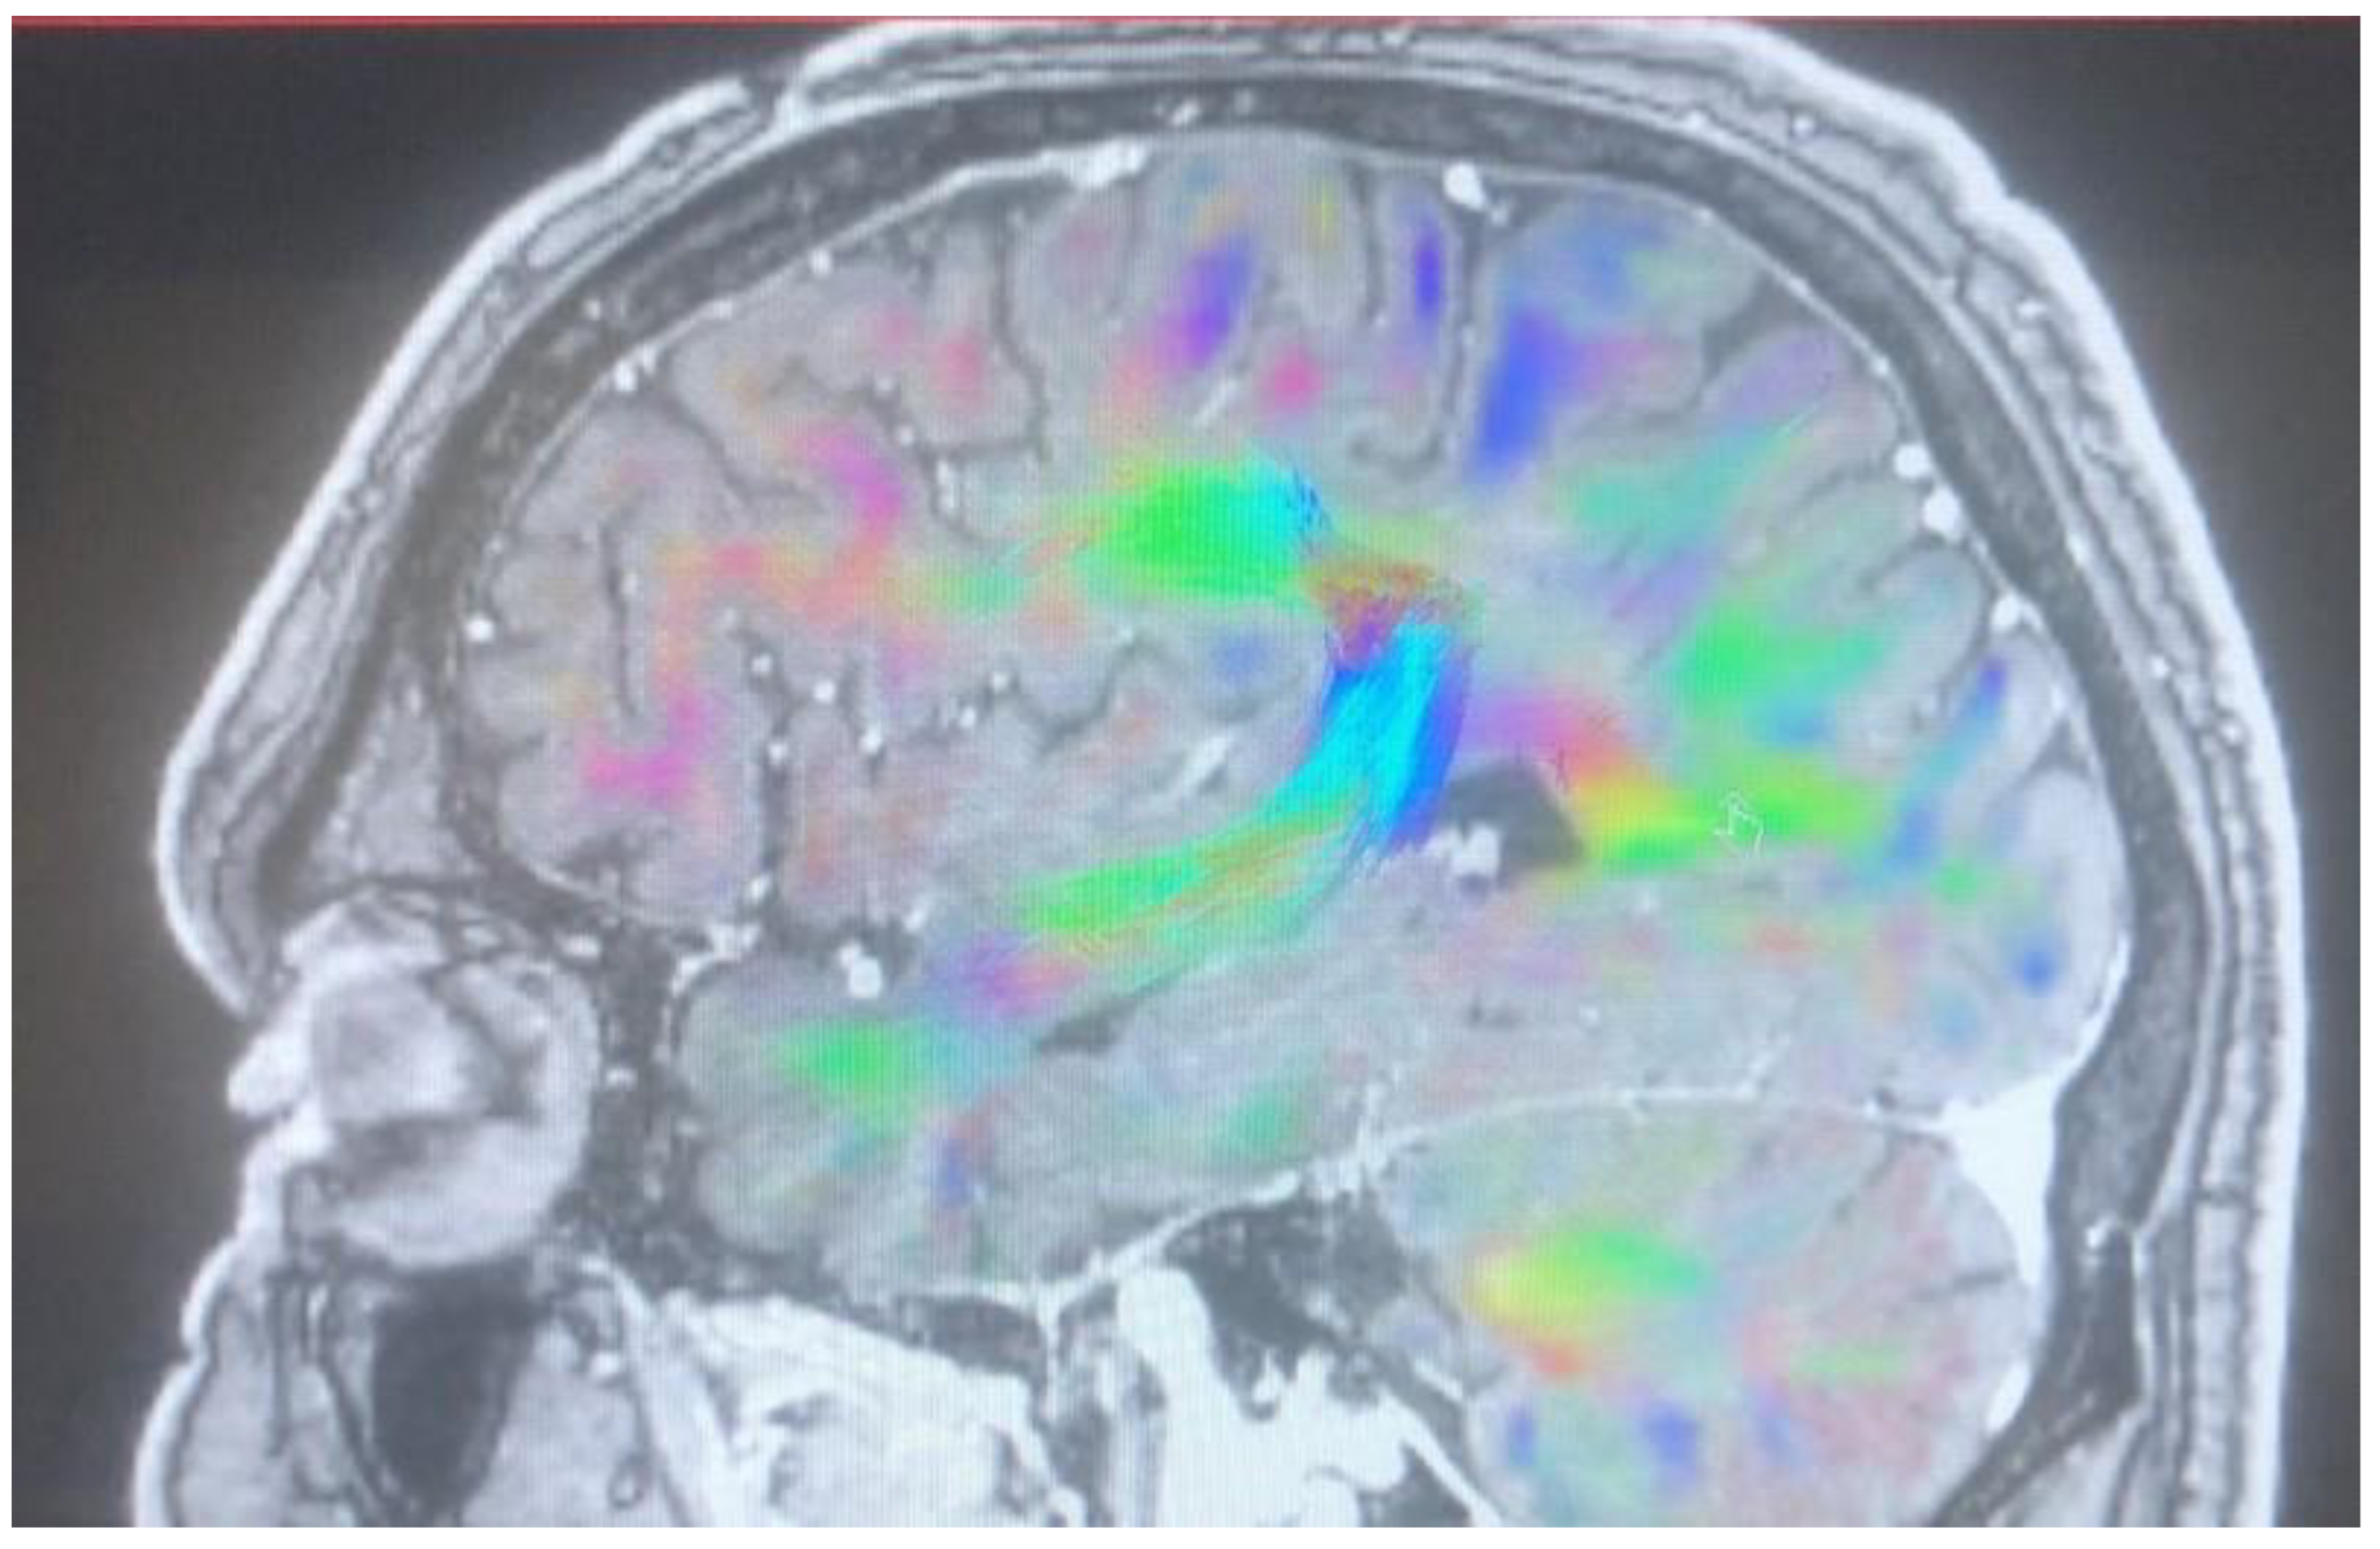

Changes in the anatomy of forceps minor before and after cingulotomy are presented in Figure 2 and Figure 3; moreover, arcuate fasciculus before and after cingulotomy is presented in Figure 4 and Figure 5.

Figure 2. Forceps minor before cingulotomy.

Brainsci 13 00044 g002